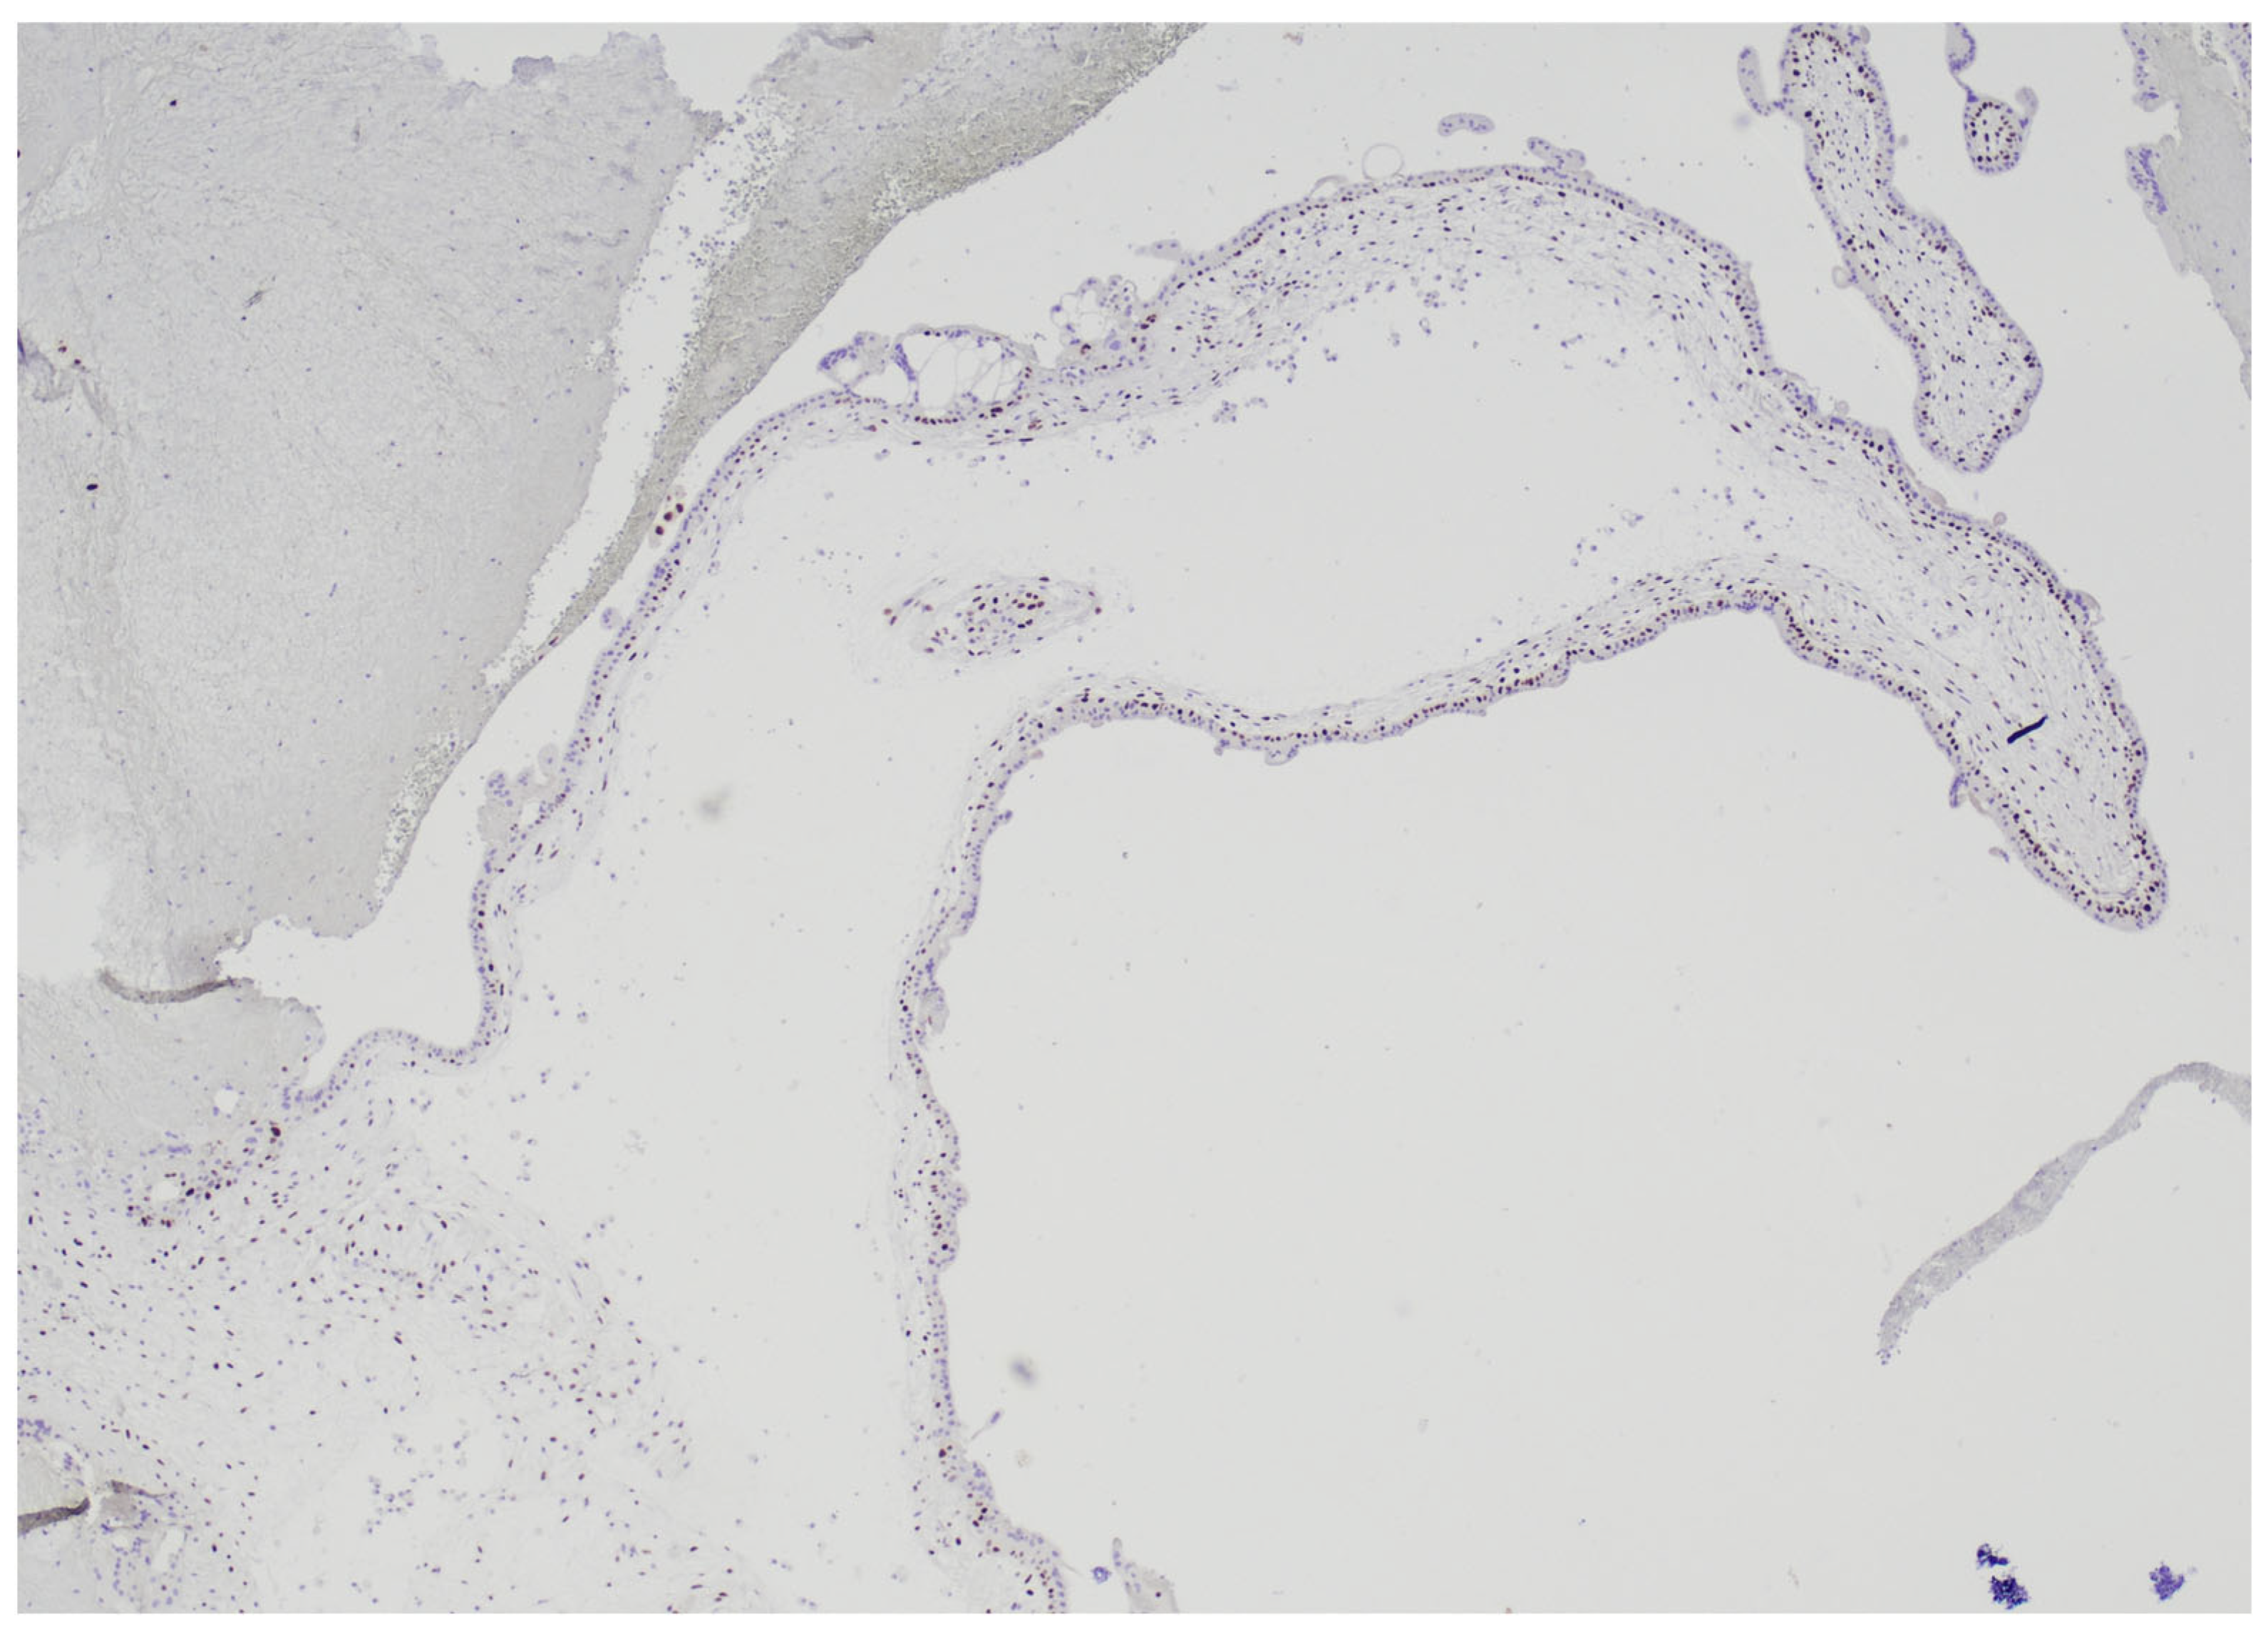

2.2. Histological Examination

2.3. HER2 FISH Analysis